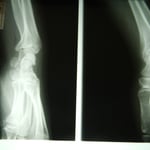

○右腓骨骨折

段差で足首をひねり下腿の二本からなる細い方の骨が折れてしまいました。受傷翌日には皮下に真っ黒な皮下出血と腫れが認められます。

一般的に整形外科では膝下から指先まで長靴のようなギプスを巻きます。ギプスの底にはヒールと言ってゴムの踵のようなものをつけます。寝る時も着けっぱなしなのでストレスがたまります。皮膚が痒くなるばかりか悪臭もしてきます。

整骨院では昔ながらの固定法で、毎日ギプスを外し浮腫を取るマッサージ、皮膚の衛生管理、超音波による骨癒合を促進させます。

ギプスを外してからリハビリでなく、受傷日からリハビリにより回復をはやめます。